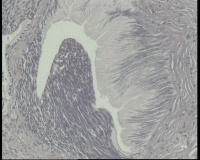

镜下见鳞状上皮大部分如(图1) ,仅局灶鳞状上皮异型(图2-4),细胞似牵拉变形,部分腺腔内见异型细胞团,这些细胞跟LEEP刀手术电凝有关系吗?这个怎么报?累腺明显,上皮图1怎么报?能报CINII—III累及腺体吗?还是宫颈高级别鳞状上皮内病变累及腺体

图4